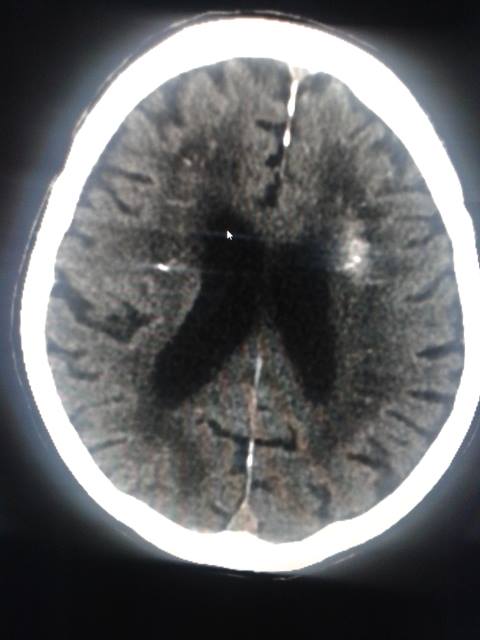

Ti ricordi del trauma cranico di ieri però. Pertanto richiedi anche una TC capo per poter procedere con sicurezza all’anticoagulazione.

TC capo: “..a sinistra, nel contesto di calcificazioni lamellari, si evidenzia area ovalare tenuemente iperdensa e asimmetrica in quadro compatibile con piccolo focolaio emorragico a tale livello..”